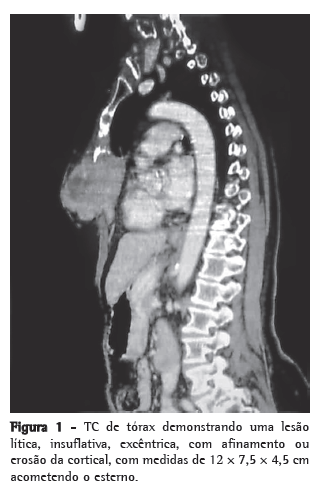

Trazia consigo um exame patológico de outro serviço, cujo resultado favorecia TCG/tumor marrom. No ambulatório do hospital de câncer de Barretos foram solicitados exames complementares (TC de tórax e testes laboratoriais séricos bioquímicos). O exame bioquímico sérico (fósforo, paratormônio e cálcio) foi normal. A TC de tórax demonstrou processo lítico, comprometendo a camada cortical do osso esterno, medindo 12 × 7,5 × 4,5 cm, além de mostrar um nódulo pulmonar no lobo inferior do pulmão esquerdo de 8 mm e inespecífico (Figura 1). A paciente foi submetida à ressecção cirúrgica tumoral com margens oncológicas em plano total (monobloco), seguida de nodulectomia pulmonar e reconstrução da parede torácica com fáscia lata. A peça cirúrgica mostrava tumor ósseo com lacunas e áreas hemorrágicas esparsas em seu interior. As margens macroscópicas se apresentavam livres (Figura 2). A paciente teve boa evolução no pós-operatório, recebendo alta no sexto dia. O exame patológico definitivo confirmou TCG, cujas margens se apresentaram livres de doença, e o nódulo pulmonar apresentava aspecto necrótico. O controle ambulatorial observou que a paciente teve melhora da dor e ausência de recorrência de doença até o quinto mês de pós-operatório.

Raramente é maligno (2-8%).(4) Incide entre a terceira e a quarta décadas de vida, excepcionalmente na sétima década.(1) Em 81% dos casos, acomete pacientes caucasianos.(1) A manifestação clínica principal é a dor local, intermitente, acompanhada ou não de aumento de volume da região afetada.(1) O tempo de história é variável.(4) Alguns pacientes procuram o tratamento devido à dor; outros, pela percepção do tumor ou por fratura patológica, relacionando o início da história clínica a algum trauma.(1) Como se observa neste presente relato, os aspectos radiográficos clássicos o definem como uma lesão lítica, excêntrica, com afinamento ou erosão da camada cortical.(1) Geralmente, acomete um único osso.(3,5-8) O TCG apresenta características clínicas, radiológicas e histológicas semelhantes às lesões tumorais e pseudotumorais, tais como o tumor marrom do hiperparatireoidismo, o cisto ósseo aneurismático, o condroblastoma epifisário, o osteoblastoma e o fibroma não osteogênico.(1) A hipótese diagnóstica de tumor marrom do hiperparatireoidismo é confirmada por alterações bioquímicas de cálcio e fósforo séricos.(1) Neste relato, foram solicitados exames bioquímicos que ajudaram a rastrear possíveis diagnósticos diferenciais, evitando outros exames. A ressonância magnética é indicada para avaliar os limites do tumor e suas características de lesão sólida homogênea, podendo apresentar áreas de conteúdo líquido, decorrente de necrose tumoral ou de associação com áreas de cisto ósseo aneurismático.(3,5-8) O mapeamento ósseo é caracterizado por uma área de hipercaptação uniforme no local afetado, indicando aumento da atividade osteoblástica reacional, e proporciona investigar outros focos.(3) Devido ao alto custo e à priorização de pacientes, esse não foi realizado neste caso. A TC de tórax mostrou-se suficiente no esclarecimento das características e dos limites da lesão, talvez favorecida pela localização anatômica, e proporcionou a avaliação conjunta de nódulo pulmonar. Sua constituição histológica é dada pela interposição de células gigantes com células espiraladas e ovoides (Figura 3).(3) Alguns autores, numa tentativa de estabelecer um prognóstico, classificam-no conferindo graus às diferentes formas, levando em consideração as características do estroma e o número de células gigantes presentes.(1) A maior ou menor quantidade de células do estroma, por si só, não caracteriza a benignidade ou a malignidade tumoral.(1) Alguns estudos atentam para possível associação de alterações cromossômicas (braço 19q) ao surgimento dessas lesões.(7) Seu comportamento é imprevisível.(1) Há relatos de transformação maligna de TCG tratados previamente com radioterapia.(1) O tratamento, sempre que possível, deve ser cirúrgico, pois essa é a única forma capaz de proporcionar a cura.(3,5-8) O controle dos pacientes operados deve incluir o acompanhamento por exames radiológicos do local operado e também dos pulmões.(1)